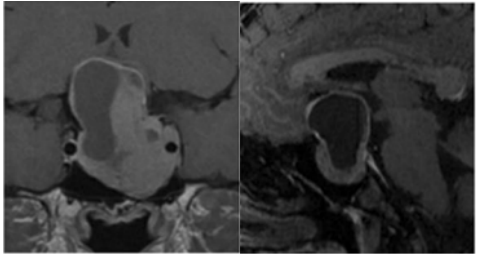

术前肿瘤持续生长进入海绵窦

INC福教授为Estelle采用标准经鼻经蝶窦入路内镜手术,随后通过移除海绵窦颈内动脉前段上的骨质进行外侧扩展术野。

内镜下经内侧三角入路

术后,Estelle动眼神经麻痹症状得到缓解,恢复过程平稳。患者维持术前药物治疗方案。病理学检查确认病变为垂体腺瘤,未见恶变特征。

经过三年随访,影像学检查未发现肿瘤复发或生长。